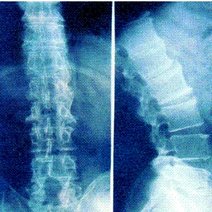

- 强直性脊柱炎,是一种慢性炎性疾病,主要侵犯骶髂关节、脊柱骨突、脊柱旁软组织及外周关节,并可伴发关节外表现。临床主要表现为腰、背、颈、臀、髋部疼痛以及关节肿痛,严重者可发生脊柱畸形和关节强直。西医学名强直性脊柱炎英文名称,所属科室内科免疫内科

- 强直性脊柱炎强直性脊柱炎(AS)是以骶髂关节和脊柱附着点炎症为主要症状的疾病。强直性脊柱炎属风湿病范畴,病因尚不明确,是以脊柱为主要病变部位的慢性病,累及骶髂关节,引起脊柱强直和纤维化

- 强直性脊柱炎强直性脊柱炎是指主要累及双侧骶髂关节、脊柱关节、外周关节和关节周围组织的一种系统炎症性疾病。临床上常见以休息时下腰部(或腰背部)、髋关节或下肢多个大关节疼痛为主要表现。

- 强直性柱炎强直性柱炎强直性柱炎(AS)是一种主侵犯柱,并累及关和周围关的慢性性炎性疾病。类湿性柱炎、类湿中心型等,现称AS。由于本病也可侵犯外周关,并在临床、放射线和病理